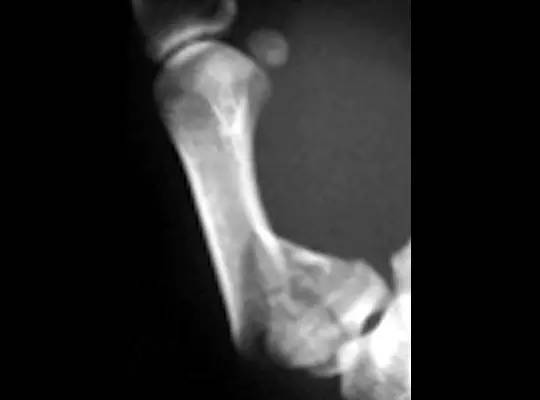

5. Hoffa 骨折

指股骨远端冠状面的骨折。

病例 1:一般股骨髁间、髁上粉碎骨折中含 Hoffa 骨折的不少见,但单纯后髁骨折则很少见。

正位片

侧位片

水平位 CT